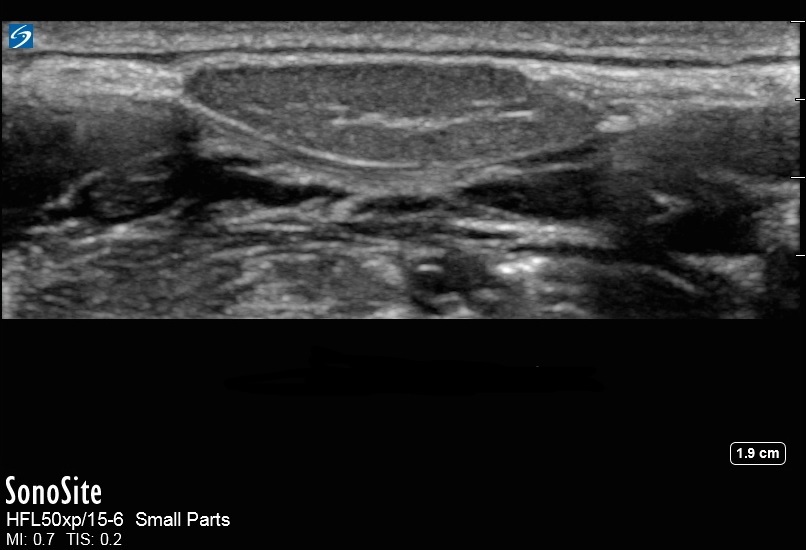

舌下腺画像